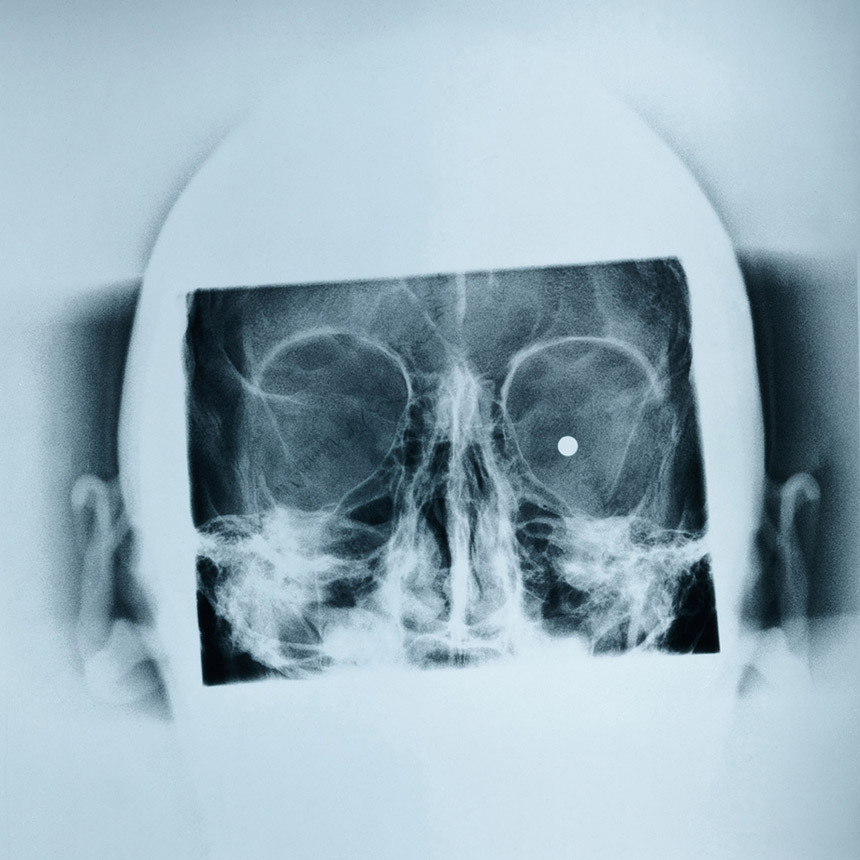

In seinen Fotoprojekten lotet Claudio Hils kontroverse Themen aus, so etwa die surrealistische Kriegsszenerie eines Truppenübungsplatzes oder die Unmenschlichkeit der Stadtarchitektur in den neuen Megametropolen. In der vorliegenden Publikation dokumentiert er die Spuren, die Jahre der Gewalt in Belfast hinterlassen haben. Die Erfahrung von Gewalt hat sich tief in das kollektive Bewusstsein eingegraben. In jedem Archiv der Stadt, das fotografische Mittel zur objektiven Beweisführung für die Auswirkungen von Gewalt verwendet, finden sich Spuren des Konflikts. Medizinische Röntgenaufnahmen zeigen den Körper als Ort von Traumata; Polizeifotos geben Tatorte genauestens wieder. Auch private und halböffentliche Sammlungen von Memorablen des Konflikts werden im Augenblick in öffentliche Archive umgewandelt. Man überführt sie in einen neuen Kontext und macht sie so zu historischen Artefakten. Archive Belfast beobachtet, wie Geschichte geschrieben wird.

Was zunächst nur als Wirrwarr aus Computerkabeln wahrzunehmen ist, entpuppt sich bei näherem Betrachten als Datenserver der Abteilung Fotografische Dokumentation der Polizeiwache Knocknagoney, Nordirland. Diese und ähnlich unerwartete Szenerien versammelt Claudio Hils in dem Bildband „Archive_Belfast“, der sich als Dokumentation der Spuren versteht, die die jahrelange Gewalt in Belfast hinterlassen hat. Claudio Hils hat für sein Buch Polizeiwachen, Krankenhäuser, Gerichtssäle und Bibliotheken nach Aktenmappen, Röntgenbildern oder Schusslöchern abgesucht und mit der Kamera festgehalten. Dabei ist es ihm gelungen, in bisher verschlossene Polizeiarchive zu gelangen; das dort gesichtete Material wird nun von Hils erneut archiviert. Auf seiner Spurensuche durchforstet der Fotograf nicht nur den öffentlichen Raum, sondern auch den privaten: Stahlrahmen im Einfamilienhaus etwa zeugen von ehemaliger Verbarrikadierung. Durch zum Teil plakative Darstellung und durch gut beobachtete Details macht Hils die Stigmatisierung jedes Winkels der Stadt durch den Nordirland-Konflikt deutlich. Auffällig ist, dass sowohl direkte Kriegsereignisse als auch Personen auf den Fotos nicht zu sehen sind. Jenseits von Klischees der medialen Repräsentation des Bürgerkriegs beschwören die Bilder Erinnerungen herauf, wobei der deutsche Fotograf vorrangig das bürokratische Gedächtnis in Szene setzt. Mit seinen unterkühlten Bildern gelingt ihm eine vortreffliche Darstellung des Verschwindens der menschlichen Individualität durch Krieg.

Fünf Jahre nach dem Belfaster Friedensabkommen begann Claudio Hils (*1962) mit einer fotografischen Spurensuche, bei der es weniger um die sichtbaren Folgen des Nordirlandkonflikts als vielmehr um die Strukturen und Denkmuster ging, die sich im Gedächtnis der Menschen festgesetzt haben. Seine Suche führte ihn auch in die Archive der Stadt. wo sich Zeichen fanden, die von den gewalttätigen Auseinandersetzungen zeugen: mit Stahlplatten versperrte Fenster, Dachkammern mit Uniformen und Musikinstrumenten, Videobänder von Überwachungskameras oder Röntgenbilder von Schussverletzungen. Hils' fotografischer Blick ordnet die Zusammenhänge neu und macht aus dem ehemals Alltäglichen der Gewalt eine noch heute konkret erlebbare, beunruhigende Erfahrung.

Ab Frühjahr 2003 suchte Claudio Hils in den Archiven einer Stadt, die Jahrzehnte lang von Gewaltausbrüchen dominiert war, nach Spuren. Fündig wurde er in den Hinterzimmern von Kliniken, Polizeiwachen, Museen und anderen öffentlichen Einrichtungen. Dabei waren ihm weniger die entdeckten Exponate selbst, als das System; mit denen sie gesichtet und gelagert werden, für die fotografische Aufarbeitung wichtig. Hils ging es um die Verwaltung des alltäglichen Grauens. Dabei machte er sich mit seiner ihm typischen Bildsprache an die Umsetzung. Hier ist das von einer Bombe zerfetzte Auto nur auf dem Polizeifoto im Treppenhaus einer Wache zu sehen, die im Hungerstreik gestorbenen Aktivisten hängen fein aufgereiht im Parteibüro an der Wand. Menschen sind auf seinen Bildern nie direkt zu sehen, sondern nur dokumentiert auf Bildern und Protokollen - mal als Ikonen heroischer Verehrung oder als Zielobjekt des Hasses. Aber auch ganz ohne Pathos als Opfer der Gewaltspirale auf Röntgenbildern des Hospitals festgehalten. Wenn Hils die stählerne Türöffnung in einer Wohnung mit Treppenaufgang und Wachsblumengesteck fotografiert, wirkt das zuerst wie ein Stilleben. Ein unspektakuläres Motiv, das beim Betrachter eher Verwirrung als Aufklärung hinterlässt, und das erst auf den zweiten und dritten Blick wichtige Details offenbart. Möchte man mehr erfahren, muss man sich intensiver mit dem Motiv auseinandersetzen. Wieso hängt die Stahltür nicht mehr im Rahmen? Wer lebt hier? Wieso überhaupt eine Stahltür in der Wohnung? Der Betrachter ist gezwungen, sich selbst ein Bild zu machen, da ihn der Fotoband zu Orten und Begleitumständen weitgehend im Unklaren lässt. Hier setzt der Fotograf das mediale Archiv des Betrachters als Ausgangsbasis voraus. Die abgespeicherten, hinlänglich bekannten Nachrichtenbilder des irischen Konfliktes im Kopf, kann er hier neue Sichtweisen erfahren. Durch diese unorthodoxe Herangehensweise an die jüngere Geschichte Belfasts macht Claudio Hils auf ebenso beklemmende wie faszinierende Weise einen für Außenstehende schwer zu verstehenden, auch religiösen Konflikt sichtbar, dessen tragischen Protagonisten hier noch einmal die Ehre erwiesen wird. Auf Tournee in der Welt Obwohl das Projekt "Archive_Belfast" auch auf Ausstellungs-Tournee . geht, sind die Arbeiten des Mengener Fotokünstlers vorläufig nicht in Süddeutschland zu sehen. Die großformatigen Exponate werden jedoch in nächster Zeit in Berlin, London, Paris, Madrid und Barcelona ausgestellt. „Archive_Belfast“ mit. 44 farbigen Abbildungen ist bereits das achte Fotobuch von Claudio Hils, der seit 1993 freiberuflich als Kommunikationsdesigner, Journalist, Fotograf, Kurator, Dozent und Ausstellungsmacher arbeitet. Reportagen von ihm wurden unter anderem in "Geo", "Globe" und "Zeit-Magazin" veröffentlicht.

Seit Jahrzehnten ist Belfast Schauplatz von Wut und Gewalt. Nun verlangt die Stadt nach Aufarbeitung, Analyse und Gedenken. Der Fotograf Claudio Hils sicherte die Spuren des Konflikts und stellt daraus ein beklemmendes, aber eindruckvolles Buch mit zuweilen schockierenden Farbfotografien zusammen: zurückgelassene Devotionalien in Archiven und Polizeistationen, in Parteizentralen und Versammlungsstuben. Die Schärpen, Fahnen und Pauken für die Aufmärsche der Oranier, in olivgrünes Leinen gebundene Jahrgänge der "Irish Times" und sogar Röntgenbilder der Schussverletzten von den Straßenkämpfen bilden einen fotografischen Nachruf auf die jüngste Vergangenheit eines schwer nachzuvollziehenden Konflikts.

Das eine Foto zeigt Kriegsspielzeug, Bomber in Tarnfarben, auf einen Haufen geworfen und in einen Plastiksack gesteckt – Geschichte eingetütet, aufgenommen im Depot des People's Museum Belfast. Das andere Foto zeigt einen verlassenen Raum, die Fenster mit Stahlplatten verschottet, die Möbel mit Stoffplanen überzogen – Geschichte abgedeckt, aufgenommen im Büro der Republikanisch-sozialistischen Partei Irlands. Claudio Hils hat die Bilder aufgenommen, für seine Fotoserie "Archive Belfast", eine mediale Auseinandersetzung mit der Frage, wie wir mit unserer Geschichte und ihren Geschichten umgehen, wie wir uns erinnern, und in welchem Verhältnis diese Memoria zum Vergessen steht – so aufregend, so anregend wie Hils hat diesen prekären Balanceakt nur W.G. Sebaldin seinen Text-Bild-Geschichten zu stellen vermocht (Hatje Cantz Verlag, Ostfildern. Ruii 2004. 120 Seiten, 35 Euro). Hils ist hinabgestiegen in die letzten Winkel der Belfaster Archive, in die öffentlichen ebenso wie in die privaten, dorthin, wo die Unordnungjede Systematik verdrängt hat, wo die Gegenstände, ihrer einstigen Bedeutung und Symbolik beraubt, verstauben – und doch niemals aufhören, von der Vergangenheit zu künden. Wie die gespenstischen Schattenaufnahmen der von Schrotkugeln durchsiebten Knochen in der Röntgenabteilung des Royal Victoria Hospitals. Die Fotos zwingen uns genau hinzusehen, Marginales, Übersehenes wahrzunehmen. So werfen sie immer wieder neue Fragen auf. Hils-ist Archäologe im besten Sinne des Wortes.